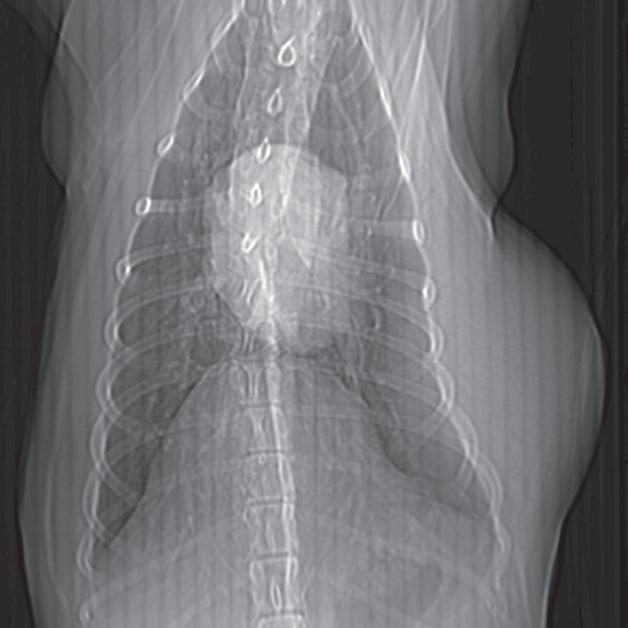

Badanie wykonano u dorosłego, kastrowanego kota domowego krótkowłosego z występującym od kilku miesięcy kaszlem i utratą masy ciała. W ostatnim czasie u pacjenta obserwowano postępujący wysiłek oddechowy. Poprzeczne obrazy TK skupione na dwóch kolejnych żebrach, widoczne od doczaszkowego do doogonowego, ukazują w części bliższej przemieszczone lewostronne złamania (a, b – duże groty strzałek). Oba złamania są minimalnie przemieszczone i mają widoczne proliferacyjne zmiany, niełączące jeszcze odłamów kostnych. Złamania dotyczą sześciu kolejnych żeber po lewej stronie (c). Zmiany w płucach obejmowały znacznego stopnia, uogólniony odczyn okołooskrzelowy (a, b), niedodmę i konsolidację płata dodatkowego płuc (b – strzałka) oraz rozstrzeń oskrzeli (a, b – małe groty strzałek). Popłuczyny oskrzelowo-pęcherzykowe (BAL) wykazały ropne zapalenie, wyhodowano szczep Mycoplasma. Założono, że złamania były wynikiem cyklicznych urazów przeciążeniowych, spowodowanych przedłużonym zwiększonym wysiłkiem oddechowym